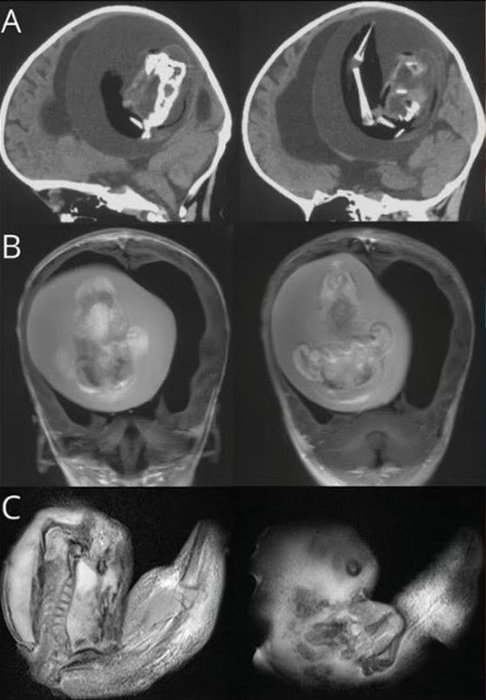

Çin'de bir yaşındaki bebeğin beyninden ikizinin fetüsü çıkarıldı. Bunun tarihte yalnızca birkaç kez yaşanan bir anomali olduğunu dile getiren uzmanlar, bebeğin kafatasının beklenenden daha geniş olması nedeniyle durumun fark edildiğini belirtti.

Tıp literatüründe yalnızca birkaç kez ortaya çıkan ilginç bir olay yaşandı. Çin'de bir yaşındaki bir bebeğin kafatasının beklenenden geniş olduğu ve motor becerilerinde sorunlar görüldüğü gerekçesi ile hastaneye kaldırılmıştı. Bebeği hastalığı şaşkına çevirdi.

Bebeğin beyninin sıkıştığı ve içinde sıvı birikimi olduğu tespit edilince ileri incelemeler yapıldı.

İncelemeler sonucunda bebeğin bir ikiz kardeşi olduğu ancak anne karnında gelişemediği için kardeşinin beyninde sıkıştığı ortaya çıktı.

Buna benzer bir olay İngiltere'de 1982'de Londra Hastanesi'ndeki bilim insanları tarafından bulunmuştu.

Çin'de 1015'te de doktorlar erkek ikizinin skrotal kesesinde doğmamış bir cenin bulmuştu.